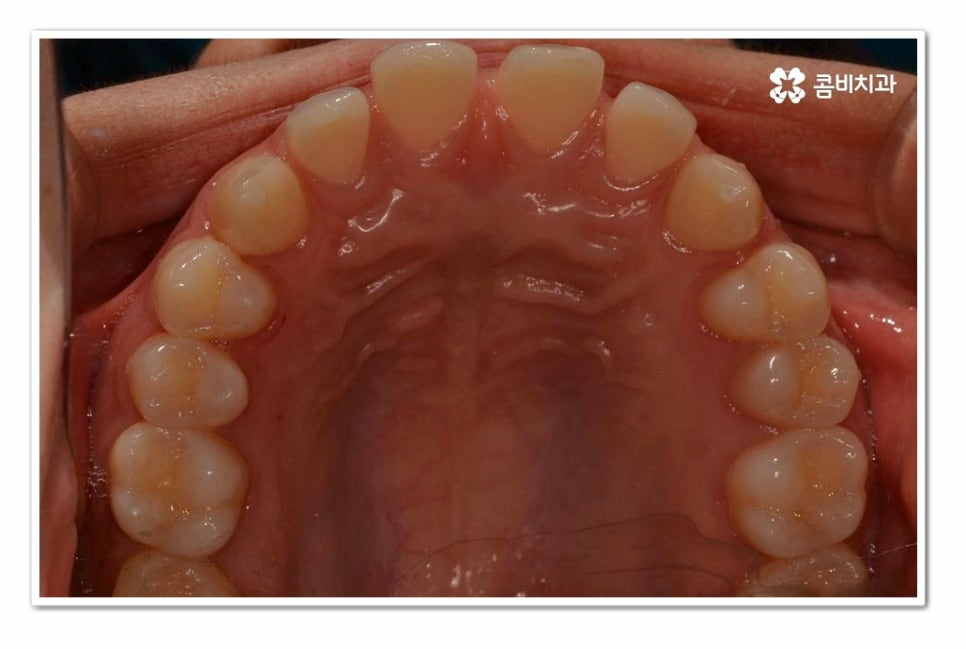

위 환자분의 경우 치아교정을 통해서 앞니 벌어짐 치료를 진행한 사례이며

치아의 이동 공간과 교합을 고려할 때 전체교정이 필요했던 사례라고 할 수 있어요.

위 환자분의 경우 윗니 만이 아니라 아랫니도 벌어져 있기 때문에

라미네이트와 같이 단기적으로 심미성을 고려한 치료보다는

치아교정을 통해 치아의 건강부터 교합, 심미성을 함께

개선할 수 있는 치료 계획을 세운 것이라 할 수 있어요.

오늘 보여드린 환자분의 케이스는 윗니와 아랫니가 모두 벌어져 있기 때문에

전체교정을 통해서 치료가 진행되었지만